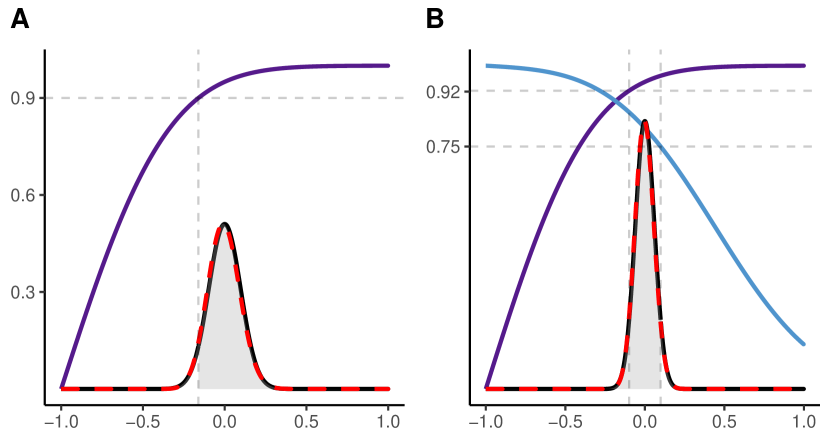

We need to be aware that even if is close to , i.e. the bias is low, the probability for a substantial deviation of the actually realized specificity from the targeted specificity might be large (Figure 1).

A) For and : The area shaded in light gray represents 95% of the area under the normal curve. I.e. there is a 95% chance of obtaining a from the test-retest study that will result in an effective specificity of greater than 90%.

B) For and : The area shaded in light gray represents 95% of the area under the normal curve. I.e. there is a 95% chance of obtaining a from the test-retest study that will result in a specificity of greater than 75%. In this case, an effective specificity of 92.27% will be reached with a certainty of 95%.

Common sample sizes in test-retest studies are around 10 and 20 [3, 12, 22, 15, 4, 21]. If the point estimator of resulting from a test-retest study with a sample size of 10 and two repeated measurements is used, the distribution of the effective specificity will have prominent tails as illustrated in Figure 1. According to (17), the lower bound of the effective specificity obtained with 95% confidence is 0.7814 and 0.8512 for a sample size of 10 and 20, respectively, which might be insufficient (Figure 4). Note that for the recommendation by Obuchowski and Bullen[24] of a sample size of 35 for test-retest studies with the probability of achieving an effective specificity below 94% is 39.74%.

However, using the mean effective specificity as sole quality criterion has limitations, since the whole distribution of the effective specificity is not properly taken into account. As illustrated in Figure 1, there is a high probability that the actually achieved effective specificity deviates strongly from its target even if the mean effective specificity may be close to the targeted specificity. Therefore, we propose a quality criterion for sample size calculations based on the probability that the effective specificity exceeds a chosen lower bound, taking into account the tails of the distribution of .